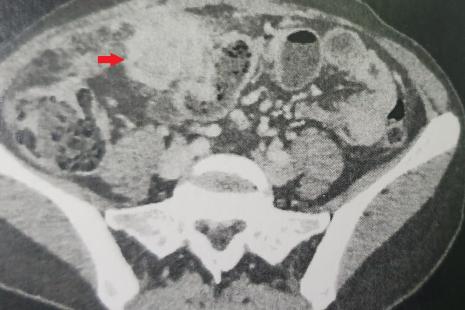

Les actinomycoses pelviennes sont des affections bactériennes rares. Chez les femmes, dans la majorité des cas, elles sont dues à un dispositif intra-utérin. La symptomatologie est très atypique avec des douleurs abdominales mal systématisées. Le diagnostic repose sur la culture de prélèvements contaminés. Le traitement repose sur l’administration de pénicilline. En cas de complications, une prise en charge chirurgicale peut être nécessaire.

Sylviane, 47 ans, consulte pour douleurs abdominales et pelviennes.

Sur le plan clinique, nous sommes surpris par la présence d’une défense au niveau de la fosse iliaque droite, mais aussi de la région hypogastrique.